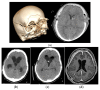

Low- or very-low-pressure hydrocephalus is a serious and rare phenomenon, which is becoming better known since it was first described in 1994 by Pang and Altschuler. Forced drainage at negative pressures can, in most cases, restore the ventricles to their original size, thus achieving neurological recovery. We present six new cases that suffered this syndrome from 2015 to 2020: two of them after medulloblastoma surgery; a third one as a consequence of a severe head trauma that required bifrontal craniectomy; another one after craniopharyngioma surgery; a fifth one with leptomeningeal glioneuronal tumor; and, finally, a patient carrier a shunt for normotensive hydrocephalus diagnosed ten years before. At the moment of development of this condition, four of them had mid-low-pressure cerebrospinal fluid (CSF) shunts. Four patients required cerebrospinal fluid (CSF) drainage at negative pressures oscillating from zero to -15 mmHg by external ventricular drainage until ventricular size normalized, followed by the placement of a new definitive low-pressure shunt, one of them to the right atrium. The duration of drainage in negative pressures through external ventricular drainage (EVD) ranged from 10 to 40 days with concomitant intracranial pressure monitoring at the neurointensive care unit. Approximately 200 cases of this syndrome have been described in the literature. The causes are varied and superimposable to those of high-pressure hydrocephalus. Neurological impairment is due to ventricular size and not to pressure values. Subzero drainage is still the most commonly used method, but other treatments have been described, such as neck wrapping, ventriculostomy of the third ventricle, and lumbar blood patches when associated with lumbar puncture. Its pathophysiology is not clear, although it seems to involve changes in the permeability and viscoelasticity of the brain parenchyma together with an imbalance in CSF circulation in the craniospinal subarachnoid space.